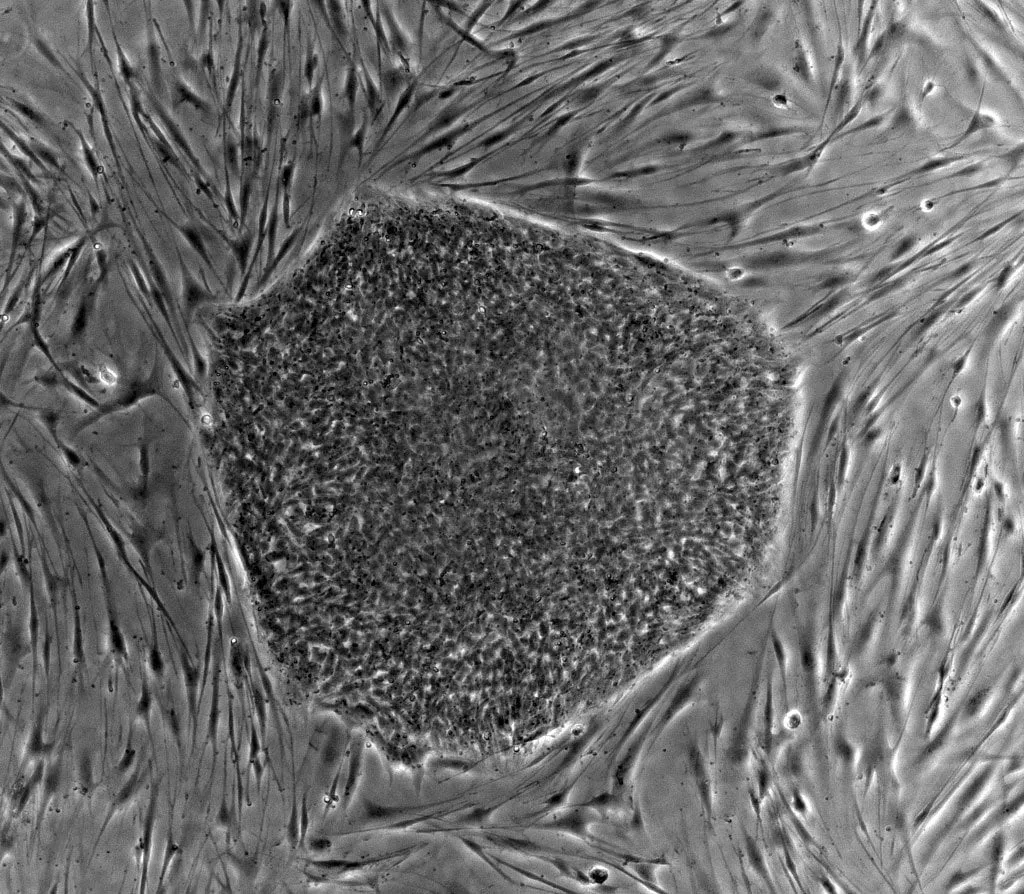

Photo : colonie de cellules souches en culture

Contrairement au greffon de cellules pancréatique qui nécessite un donneur et s’assortit de risque de rejet, pouvoir fabriquer des nouvelles cellules pancréatiques saines à partir de cellule souche est aujourd’hui la voie d’avenir pour traiter le diabète.

Les recherches, en cours, visent à multiplier en laboratoire les cellules souches (les cellules qui se trouvent en chacun de nous et qui génèrent toutes les cellules différenciées dont nous avons besoin) capables de produire l’insuline.

Les premiers essais cliniques sont d’ores et déjà concluants et laissent envisager, dans un avenir assez proche, une révolution dans le traitement du diabète.